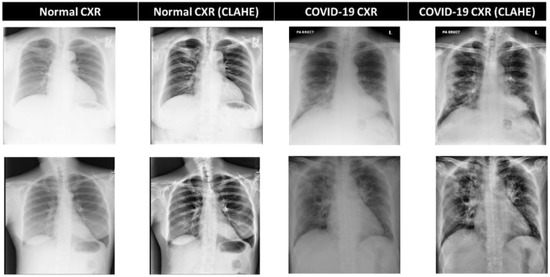

3.3. CXR Preprocessing